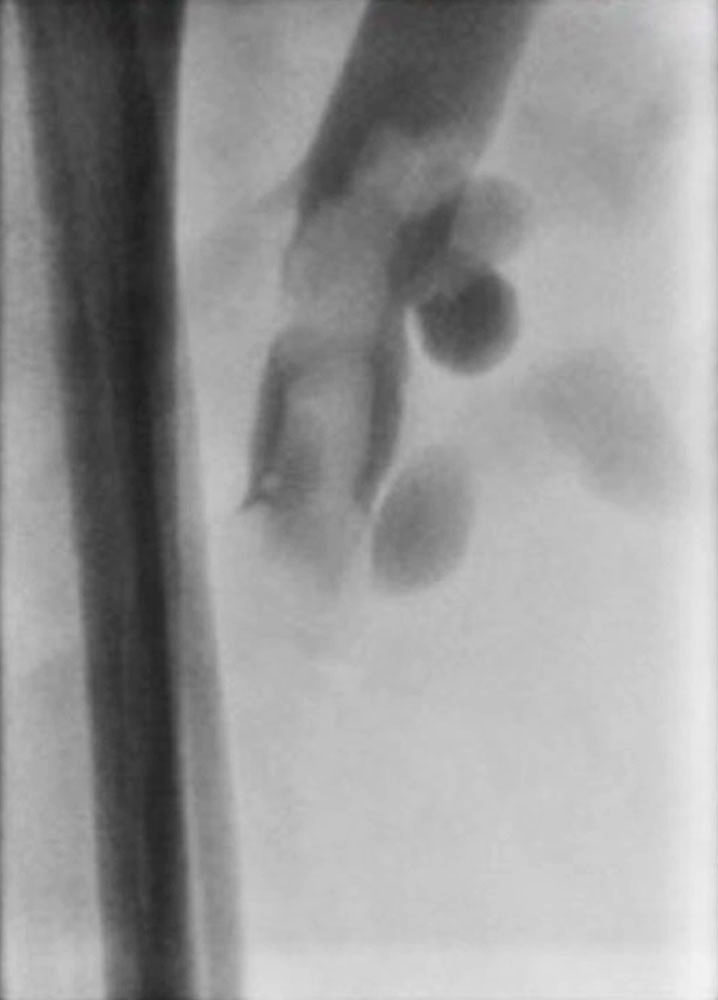

Phlebography has been almost entirely replaced by ultrasound, CT or MR phlebography for the diagnosis of phlebothrombosis and is no longer indicated. Phlebography nowadays is mostly performed as varicography in the direct puncture technique in the context of interventional procedures. In this situation the thrombus is visualized as an intraluminal contrast medium filling defect in the vein.

Via a similar mechanism, thromboembolism in venous malformation of the intestine can also lead to central dislodgement of a thrombus, in this case into the portal vein system of the liver with subsequent portal vein thrombosis.